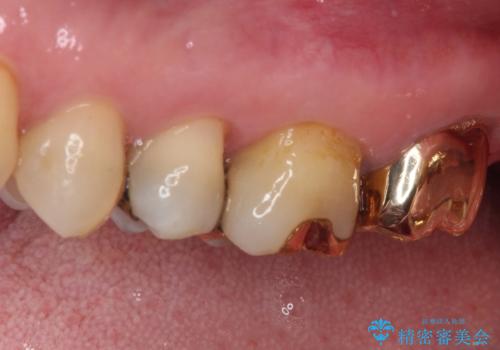

上の奥歯であることから、審美性よりも機能性を優先され、ゴールドクラウンを選択されました。

装着後の違和感など一切なく、見た目もほとんど気にならないとのことで、患者様には大変満足していただけました。